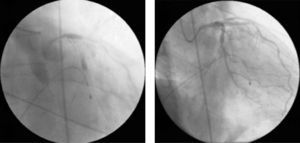

Cardiac catheterization was performed the following day, which revealed focal type A lesions in the proximal left anterior descending artery (LAD) and mid circumflex artery (Fig. 1).